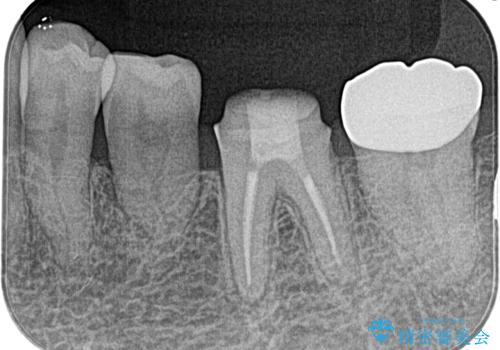

奥歯がズキズキ痛い 根管治療

担当医 河口智英